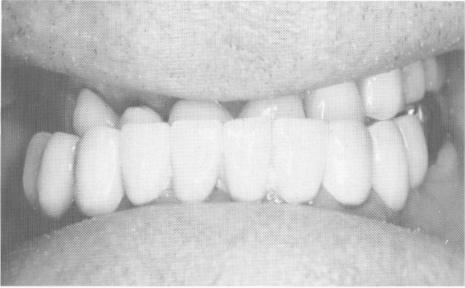

Fig. 15-30. A, The two mandibular unilateral partial dentures are cemented into position with hard cement. B to D, The completed case shows the elimination of the Class III malocclusion.